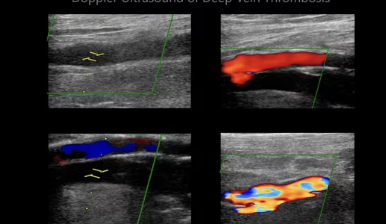

하지정맥 초음파 검사는 하지정맥류 진단의 가장 기본적이고 중요한 검사입니다. 혈관 초음파를 통해 다리 정맥의 상태, 혈액 역류 여부, 혈전 유무 등을 확인하여 정확한 진단을 내릴 수 있습니다.